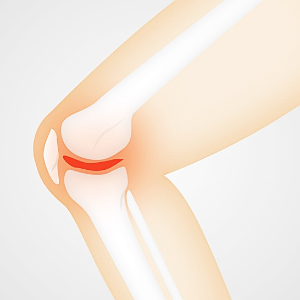

6. 퇴행성 관절염

퇴행성 관절염은 나이가 들어가면서 뼈, 인대, 근육 등의 조직이 퇴행하고 연골이 점차적으로 닳아서 염증이 발생하여 통증을 유발하는 상태를 말합니다. 주로 노년층에서 발생하는 이 질환은 노화와 밀접한 관련이 있습니다. 대부분 무릎에서 증상이 나타나지만, 어깨, 손가락, 척추 등 다른 관절 부위에서도 발생할 수 있어 항상 주의해야 합니다.